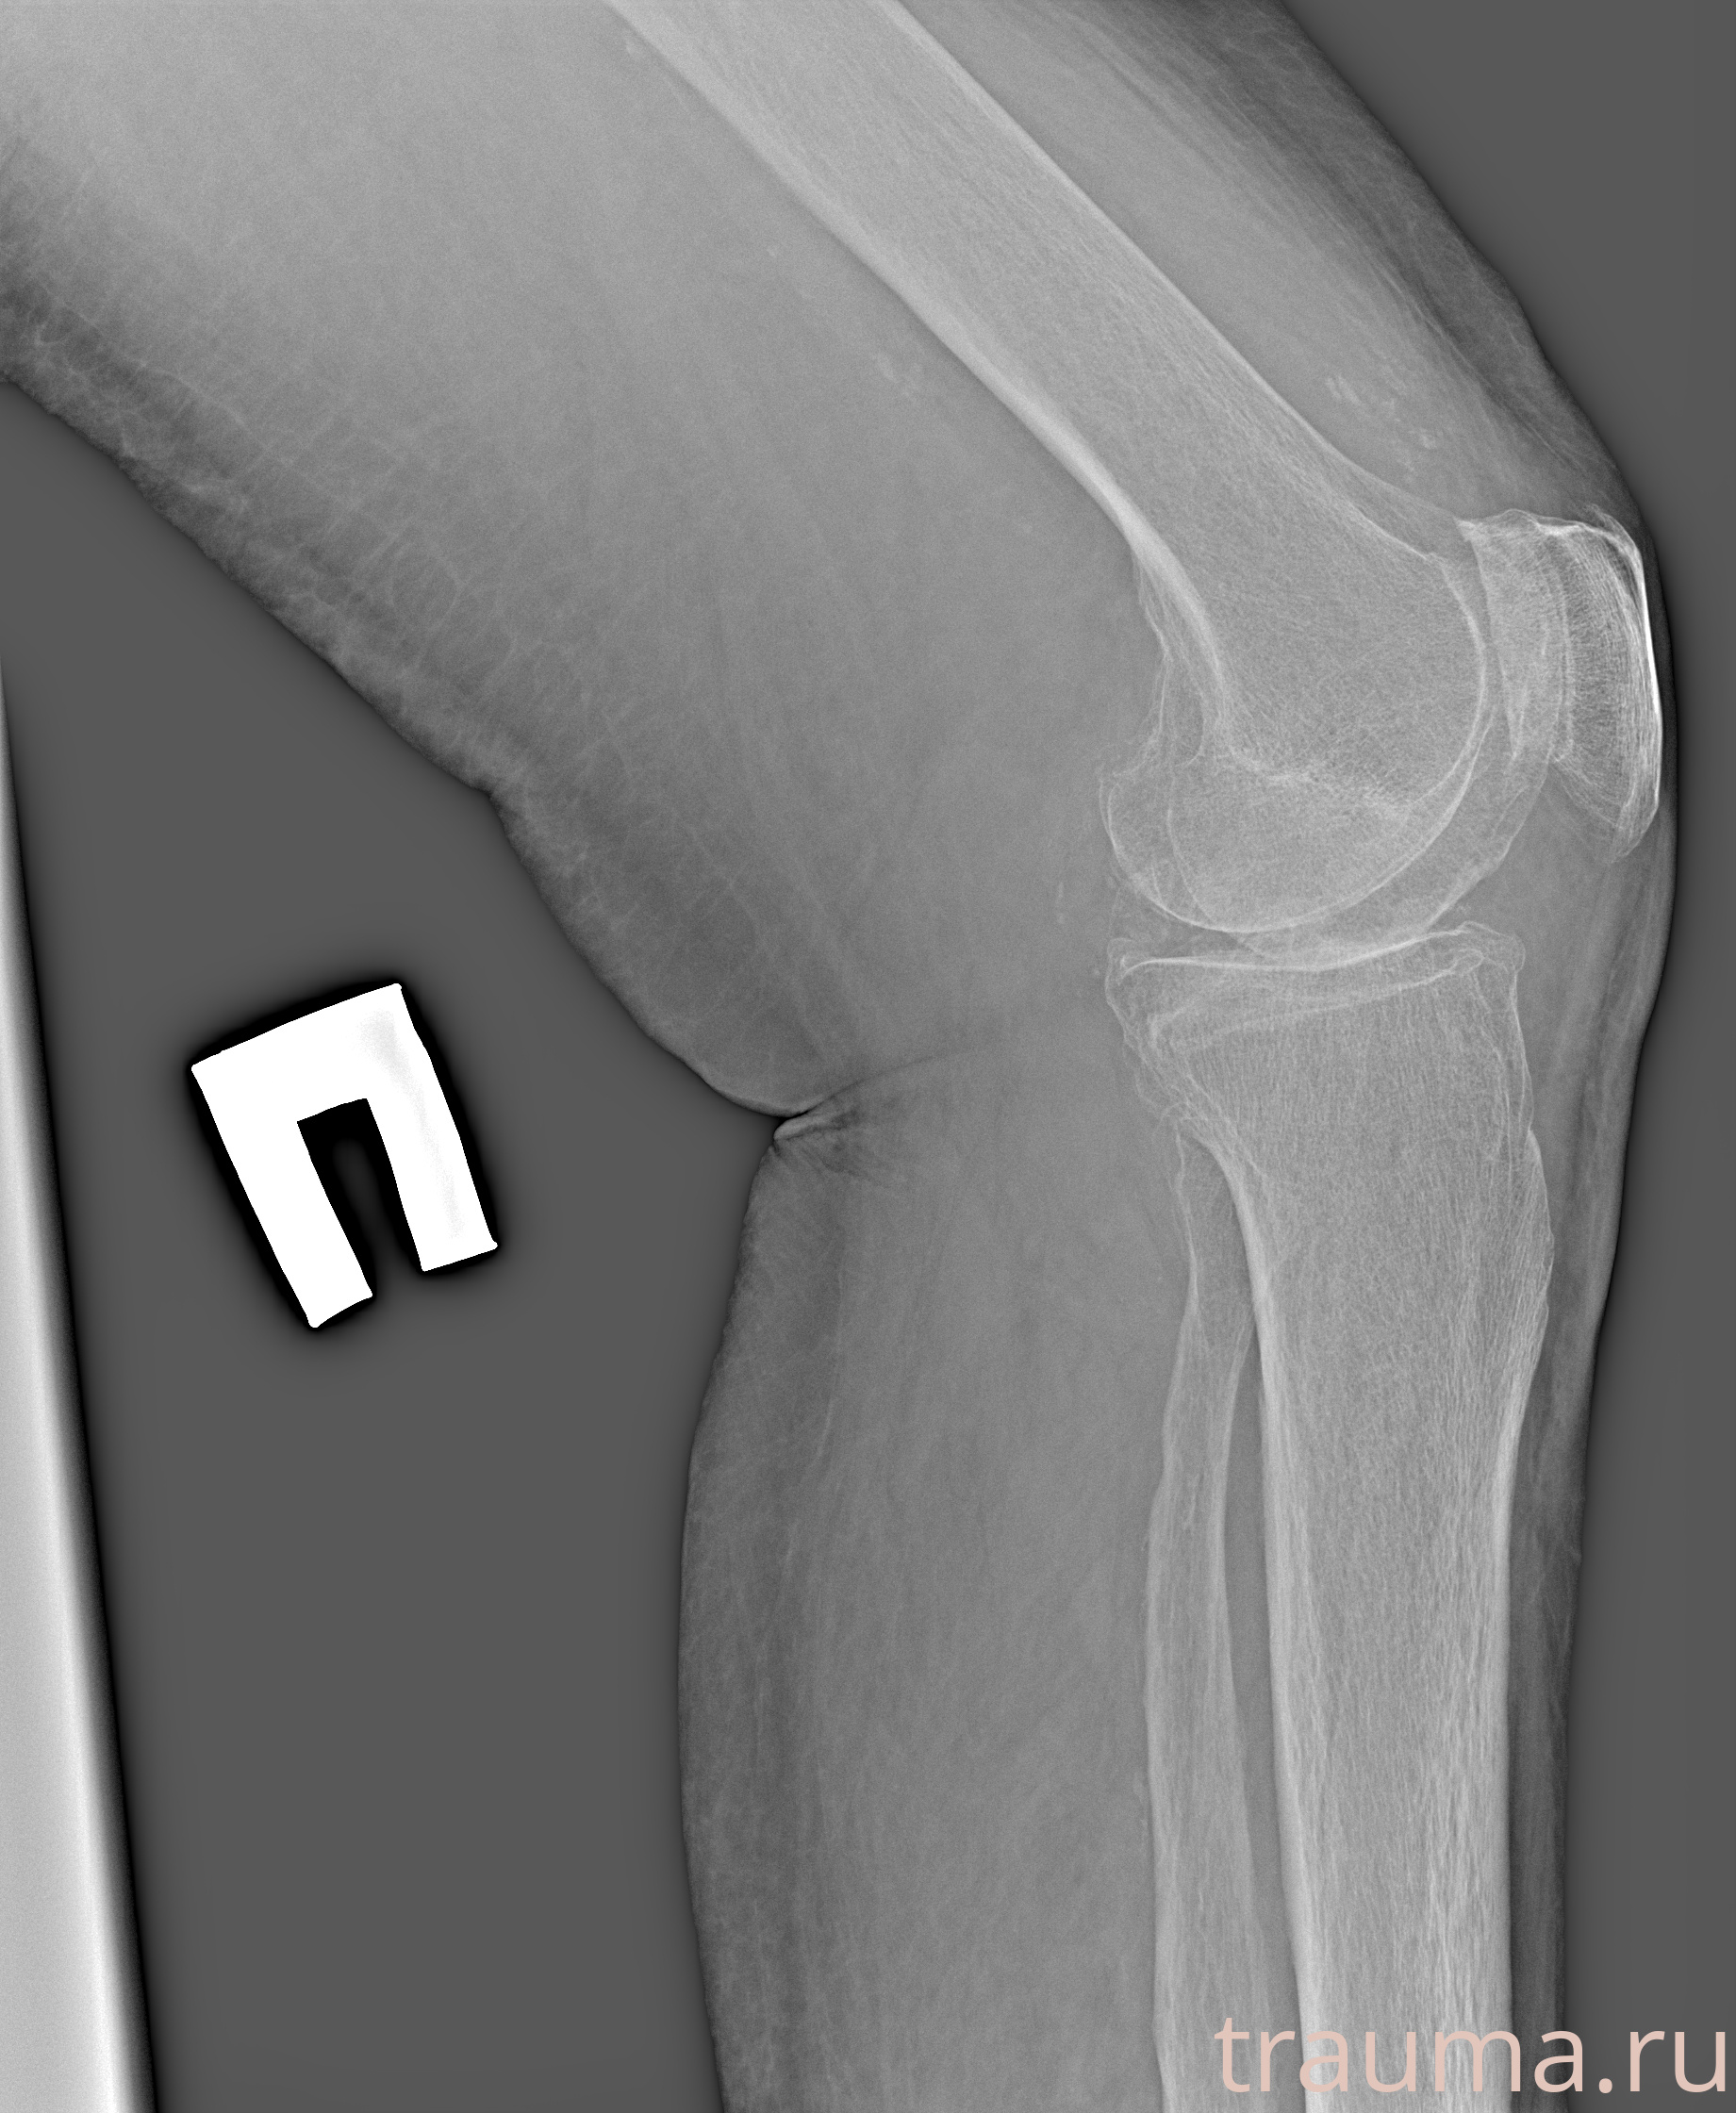

Рентгенограммы

Рентген на дому: по вашему адресу приезжает врач-рентгенолог, травматолог-ортопед с мобильным рентгеновским аппаратом, проводит диагностику травмы или заболевания, делает необходимые рентгенограммы, дает рекомендации по дальнейшему лечению. Получить качественные снимки в домашних условиях возможно благодаря уникальной методике, разработанной МосРентген Центром для института  Склифосовского